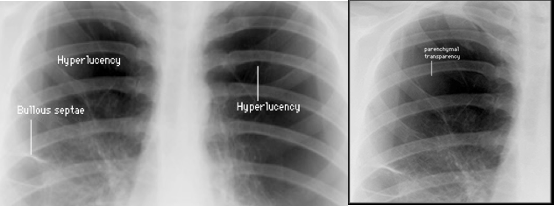

C- Chest X-ray reveals:

- Hyperlucency of lung fields

- Low standing and limited mobility of diaphragm

- Expanded intercostal spaces

- Horizontal rib position.